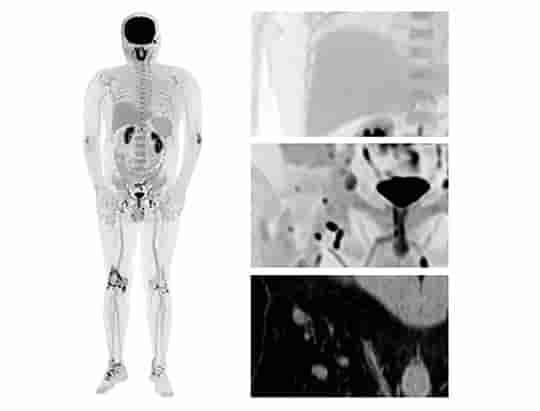

Przejrzystość obrazów uzyskiwanych z użyciem uMI Panorama wykracza poza pojedynczy parametr. System zapewnia wynoszącą 2,9 mm rozdzielczość PET wg NEMA oraz rozdzielczość czasową poniżej 200 ps, a 160-warstwowy tomograf komputerowy wykonuje pełny obrót w czasie 0,25 s z rozdzielczością przestrzenną 0,22 mm, gwarantując wysoką dokładność ilościową i wykrywalność małych zmian.